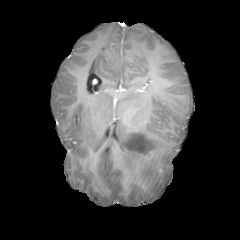

Figure 1: Example of moving (top) and fixed (bottom) image pairs. From left to right: brain MRI (T2w, T1w, T1Gd), abdomen CT from different subjects, retinal OCTA choroid, and retinal OCTA SCP scans

To address this problem, we propose a meta-learning-based registration meth-od that can efficiently use data from different domains. Specifically, we integrate an unsupervised learning-based registration model in a gradient-based meta-learning framework. The registration model is first trained using multiple registration datasets and then performs task-level learning using the multi-task data. The meta-learner finds an initialization point which can quickly adapt to various registration problems. After that, fine tuning is performed with the data of the target domain and applied to the test set. To demonstrate superiority, we trained the model for various 2D registration tasks from retinal Optical Coherence Tomography Angiography (OCTA) choroid, abdomen CT, and brain MRI scans and tested it on a registration of retinal OCTA Superficial Capillary Plexus (SCP) scans as shown in Fig. 1.

In our experiment, we used four datasets including retinal OCTA SCP, retinal OCTA choroid, abdomen CT, and Brain MRI. Both OCTA SCP and choroid datasets contained 368 moving and fixed image pairs collected from local university hospital, some of which were taken from same subjects at different times. The abdomen CT and brain MRI images were obtained from public Decathlon dataset [15]. Here, we define three tasks according to modality (T1w, T1Gd, and T2w) from the brain MRI dataset and two tasks in the abdomen CT dataset. Each 3D volume was divided in multiple axial slices and adjacent two slices were defined as a (M,F)𝑀𝐹(M,F) pair. All images were resized to a size of 400×400400400400\times 400 and histogram equalization was applied. Also, the range of intensity was rescaled to [0,1]. For training, we defined a set of five tasks as the source task set Tsource=subscript𝑇𝑠𝑜𝑢𝑟𝑐𝑒absentT_{source}= TbrainT1subscript𝑇𝑏𝑟𝑎𝑖𝑛𝑇1T_{brainT1}, TbrainT1Gdsubscript𝑇𝑏𝑟𝑎𝑖𝑛𝑇1𝐺𝑑T_{brainT1Gd}, TbrainT2subscript𝑇𝑏𝑟𝑎𝑖𝑛𝑇2T_{brainT2}, Tabdomensubscript𝑇𝑎𝑏𝑑𝑜𝑚𝑒𝑛T_{abdomen}, TChoroidsubscript𝑇𝐶𝑜𝑟𝑜𝑖𝑑T_{Choroid}. For evaluation, retinal OCTA SCP dataset was used as target domain data Dtargetsubscript𝐷𝑡𝑎𝑟𝑔𝑒𝑡D_{target}. It was divided into a fine-tuning set Tfinetunesubscript𝑇𝑓𝑖𝑛𝑒𝑡𝑢𝑛𝑒T_{fine-tune} (294 pairs) and a test set Ttestsubscript𝑇𝑡𝑒𝑠𝑡T_{test} (74 pairs). For evaluation, we manually labeled 20similar-to\sim30 bifurcation points on image pairs in Ttestsubscript𝑇𝑡𝑒𝑠𝑡T_{test}.